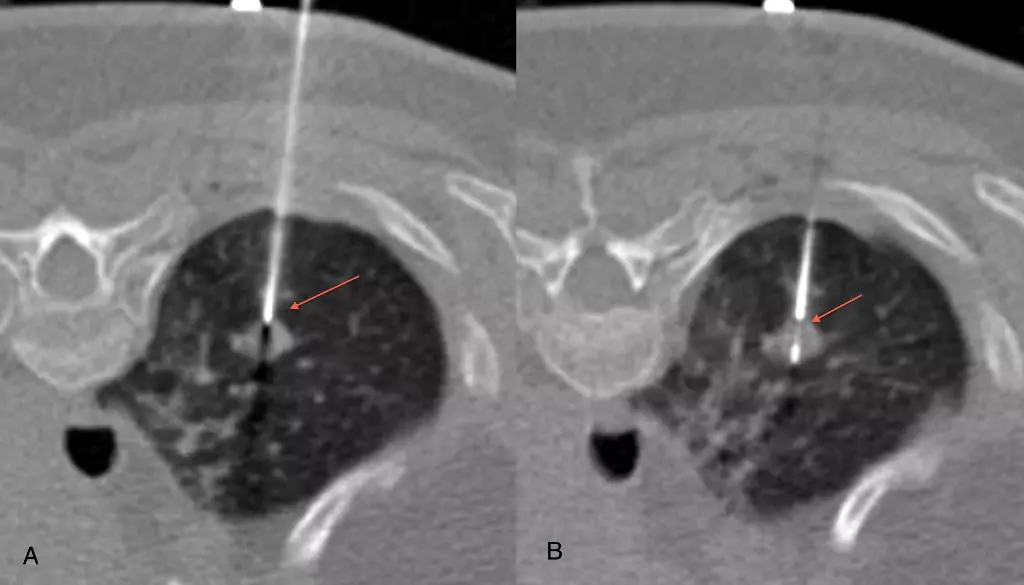

CT Guided Biopsies

We have pioneered the use of routine core biopsies as against fine-needle aspirations in different parts of the body, especially the lungs.